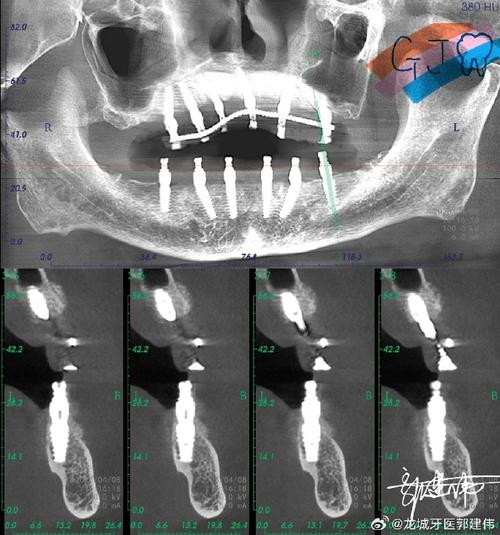

- 术前评估:通过CBCT(锥形束CT)测量骨缺损的体积、密度及与重要解剖结构(如下牙槽神经、上颌窦)的关系,制定个性化植骨方案。